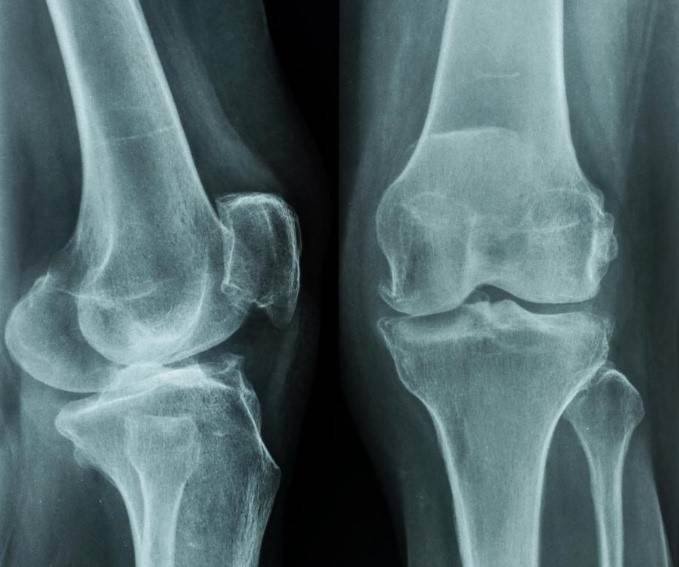

جراحی پارگی رباط صلیبی زانو: نحوه انجام و مراقبت های بعد از عمل

در میان زانو دو رباط که به صورت صلیبی از روی هم رد میشوند، استخوان ران (فمور) را به استخوان درشتنی (تیبیا) متصل میکنند و استخوانها را در جای خود ...

علائم، علت و درمان ژنورکورواتوم یا عقب زدگی زانو در کودکان و بزرگسالان

ژنورکورواتوم زانو نوعی تغییر شکل در مفصل زانو است، به طوری که زانو به عقب خم میشود. در این تغییر شکل، کشیدگی بیش از حد در مفصل تیبیوفمورال رخ میدهد...